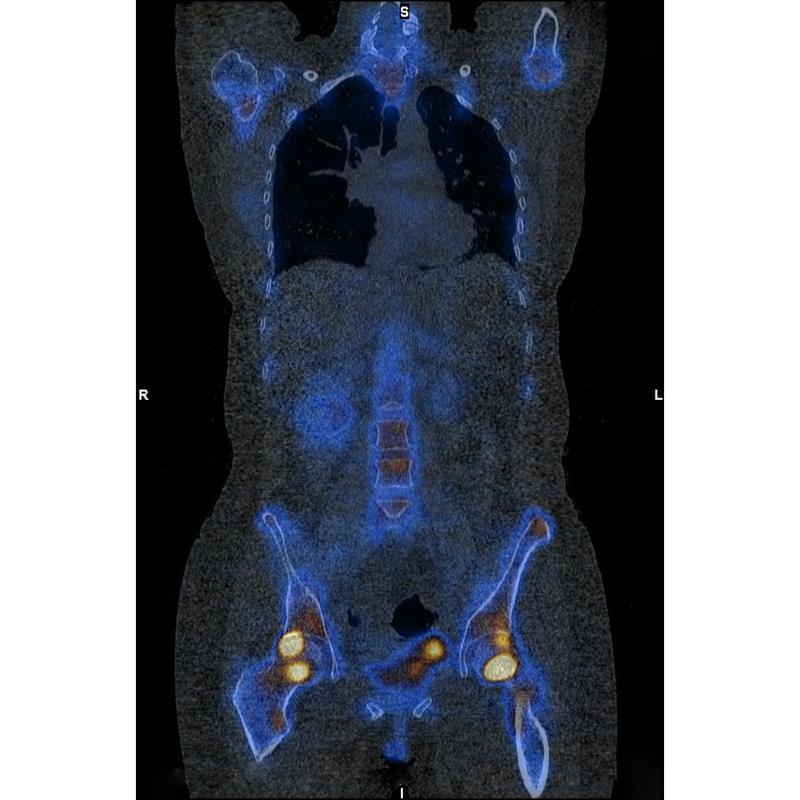

„Eines dieser intravenösen Eisenpräparate, die Eisencarboxymaltose, hat jedoch eine bedeutsame Nebenwirkung: Bei 50 bis 75 Prozent der Patient:innen sinkt der Phosphatspiegel im Blut deutlich ab. Dies kann zu Muskelschwäche und Knochenerkrankungen führen“, weiß der Gastroenterologe und Hepatologe Heinz Zoller. Seit 2019 leitet er das „CD-Labor für Eisen- und Phosphatbiologie“ an der Medizin Uni Innsbruck, in dem der Zusammenhang von Eisenmangel, der Behandlung mit intravenösem Eisen und der bei bestimmten Präparaten daraus resultierenden unerwünschten Senkung des Phosphatspiegels erforscht wird.

Zur Aufklärung dieses Mechanismus setzte das Team um Heinz Zoller und Sonja Wagner im CD-Labor verschiedene Methoden zur Analyse der Knochenentwicklung und Knochenstruktur ein. „Die Ergebnisse waren überraschend: Die Nebenwirkungen scheinen durch die besonders starke Anreicherung von Eisencarboxymaltose im Knochen bedingt zu sein, was dort zu einer verminderten Kollagenbildung führt. Darüber hinaus weisen molekulare Untersuchungen auf eine deutliche Verminderung der Knochenneubildung nach der Gabe von Eisencarboxymaltose hin“, beschreibt Sonja Wagner die weitreichenden Erkenntnisse. Die Symptome eines erniedrigten Phosphatspiegels im Blut sind unspezifisch und können sich als Schwäche, Erschöpfung oder verminderte Belastbarkeit äußern. Da diese Symptome auch denen eines Eisenmangels stark ähneln kann eine Hypophosphatämie und deren Folgen lange unbemerkt bleiben.

Um die klinische Bedeutung dieser beobachteten Veränderungen besser einordnen zu können, untersuchte das Team des CD-Labors gemeinsam mit Kolleg:innen der Medizin Uni Innsbruck und in Zusammenarbeit mit der Universitätsklinik Schleswig-Holstein in Kiel, dem Ludwig Boltzmann Institut für Osteologie in Wien und der Cornell University in New York insgesamt mehr als 20.000 Patient:innen, die mit einem der genannten Eisenpräparate behandelt worden waren. Die, im anerkannten Fachjournal Blood veröffentlichte Beobachtungsstudie ergab, dass eine intravenöse Eisentherapie mit Eisencarboxymaltose im Vergleich zu einer Therapie mit Eisenderisomaltose mit einem mehr als doppelt so hohen Risiko für Knochenbrüche verbunden ist.

„Wir schließen daraus, dass mit der Gabe von Eisencarboxymaltose molekulare Veränderungen ausgelöst werden, die unabhängig vom Phosphatspiegel die Knochenstruktur schwächen und folglich einen niedrigen Phosphatspiegel verursachen können. Damit wäre abgesenktes Phosphat im Blut nicht allein Ursache der Knochenschädigung, sondern auch Ausdruck eines bereits laufenden Prozesses im Knochen selbst“, betont Studienleiter Heinz Zoller. Die Wahl des Eisenpräparats könnte damit nicht nur darüber entscheiden, wie rasch sich ein Eisenmangel behandeln lässt, sondern auch darüber, ob sich im Knochen eine Form biologischer Ermüdung entwickelt, die lange unbemerkt bleibt. Die Knochenbrüche treten typischerweise Wochen oder Monate nach der eigentlichen Eisen-Therapie auf.